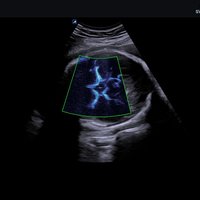

Das X-CUBE 70 fügt sich nahtlos in die neue X-CUBE Serie ein. Wie bereits das X-CUBE 90 so nutzt auch das X-CUBE 70 Farbdopplersystem die Bildverarbeitungstechnologien eines Premiumsystems, eine Vielzahl neuer Breitband-Schallköpfe mit X+ Crystal SignatureTM Technologie und neuen technischen Raffinessen.

X+ Architecture

Die X+ Architecture ist eine erstklassige Imaging-Plattform, die durch die Kombination von X+ Crystal Signature™, der Schallkopftechnologie mit hoher Sensitivität und Breitbandigkeit, und X+ FIT, ALPINIONs modernster Beamforming- und Datenverarbeitungstechnologie, geschaffen wurde.

X+ FIT ist eine neue Technologie, die den Schallstrahl scharf fokussiert sendet, ein großes Datenvolumen empfängt und mit hoher Geschwindigkeit verarbeitet. Darüber hinaus nutzt X+ Crystal Signature™ Einkristalle in den Schallköpfen, um eine hervorragende Brillanz zu erzielen und die Diagnosemöglichkeiten zu erweitern.